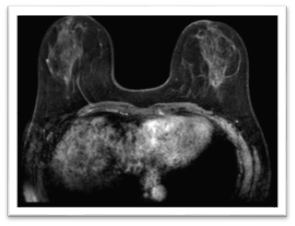

The local assessment of primary disease at the breast level was complemented with a magnetic resonance imaging (MRI) that showed a 15 mm focal non-mass enhancement in the right breast and extensive segmental non-mass enhancement of 49 mm in the left breast consistent with the lesion already biopsied (BIRADS 6), as well as suspicious-looking left axillary nodes (Figure 5).

Figure 5 MRI after neoadjuvant treatment

Complete radiological response

After six months of systemic treatment, a new MRI of the breast was performed, showing a complete radiological response (Figure 5).